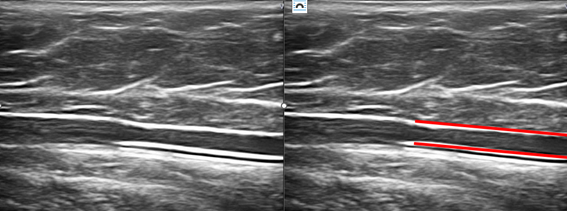

The patient is prepared for percutaneous puncture, with sterilization of the area with Chlorhexidine, and the puncture is performed under ultrasound control using the Seldinger technique with a 21G x 5, 8 or 12 cm Arrow catheter. (Figures 3-5)

Figure 5B Ultrasound image in longitudinal section showing position of the endoluminal Arrow catheter.

Once the vessel has been catheterized, the tip of the catheter is placed 10 cm from the femoral saphenous confluent.